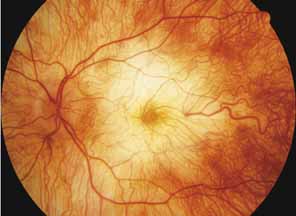

Progressive bifocal chorioretinal atrophy is a rare autosomal dominant disorder mapped to chromosome 6q33,34 that was first described by Douglas, Waheed, and Wyse35 in a large Scottish family in 1968. Thirty-three of 91 family members were affected. The authors classified the disease into three stages (Fig. 6). Stage 1, which lasts from birth to age 14 years, involves a temporal focus of atrophy of retinal and choroidal tissue in the macula that continues to slowly enlarge with time. The upper, nasal, and lower edges of the temporal lesion are well defined, whereas the temporal edge is serrated and indistinct. Stage 2, which lasts from age 15 years to age 45 years, is associated with a second focus of atrophy nasal to the disc, hence the term bifocal in the name. At the end of this stage, the nasal focus is about three disc diameters in size. Stage 3, which occurs after 45 years of age, is associated with further expansion of the temporal and, especially, the nasal focus, leaving only a vertically oriented one- to two-disc-diameter swath or band of intact retina and choroid extending from the disc to each equator superiorly and inferiorly. Visual acuity was markedly subnormal compared with early years, but no patients lost all vision. All patients had coarse nystagmoid eye movements that precluded measurement of visual fields. Most patients were myopic. The ERG b-wave amplitude was subnormal but not unrecordable by a non-Ganzfeld single-flash technique.